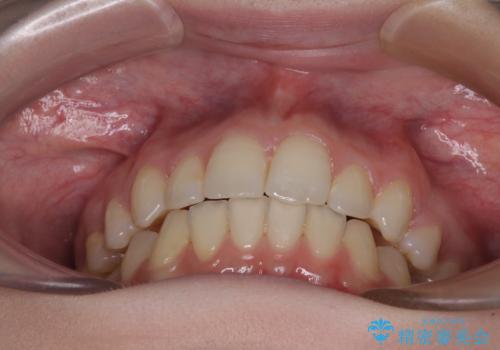

下顎の骨格的なズレが大きかったため、上下歯列のバランスが取れるか心配でしたが、上下ともに左右対称に近い歯列で治療を終えることができました。